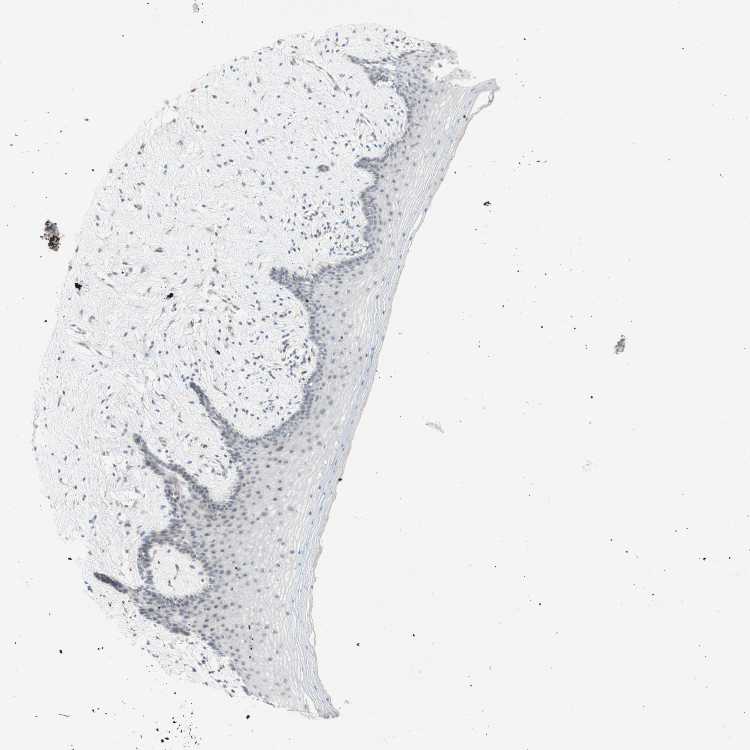

VAGINA - Antibody stainingi

Antibody staining in the annotated cell types in the current human tissue is reported as not detected, low, medium, or high, based on conventional immunohistochemistry profiling in selected tissues. This score is based on the combination of the staining intensity and fraction of stained cells.

Each image is clickable and will lead to virtual microscopy that enables deeper exploration of all samples and also displays staining intensity scores, fraction scores and subcellular localization as well as patient and tissue information for each sample.

Antibody HPA011070

Squamous epithelial cells Not detected